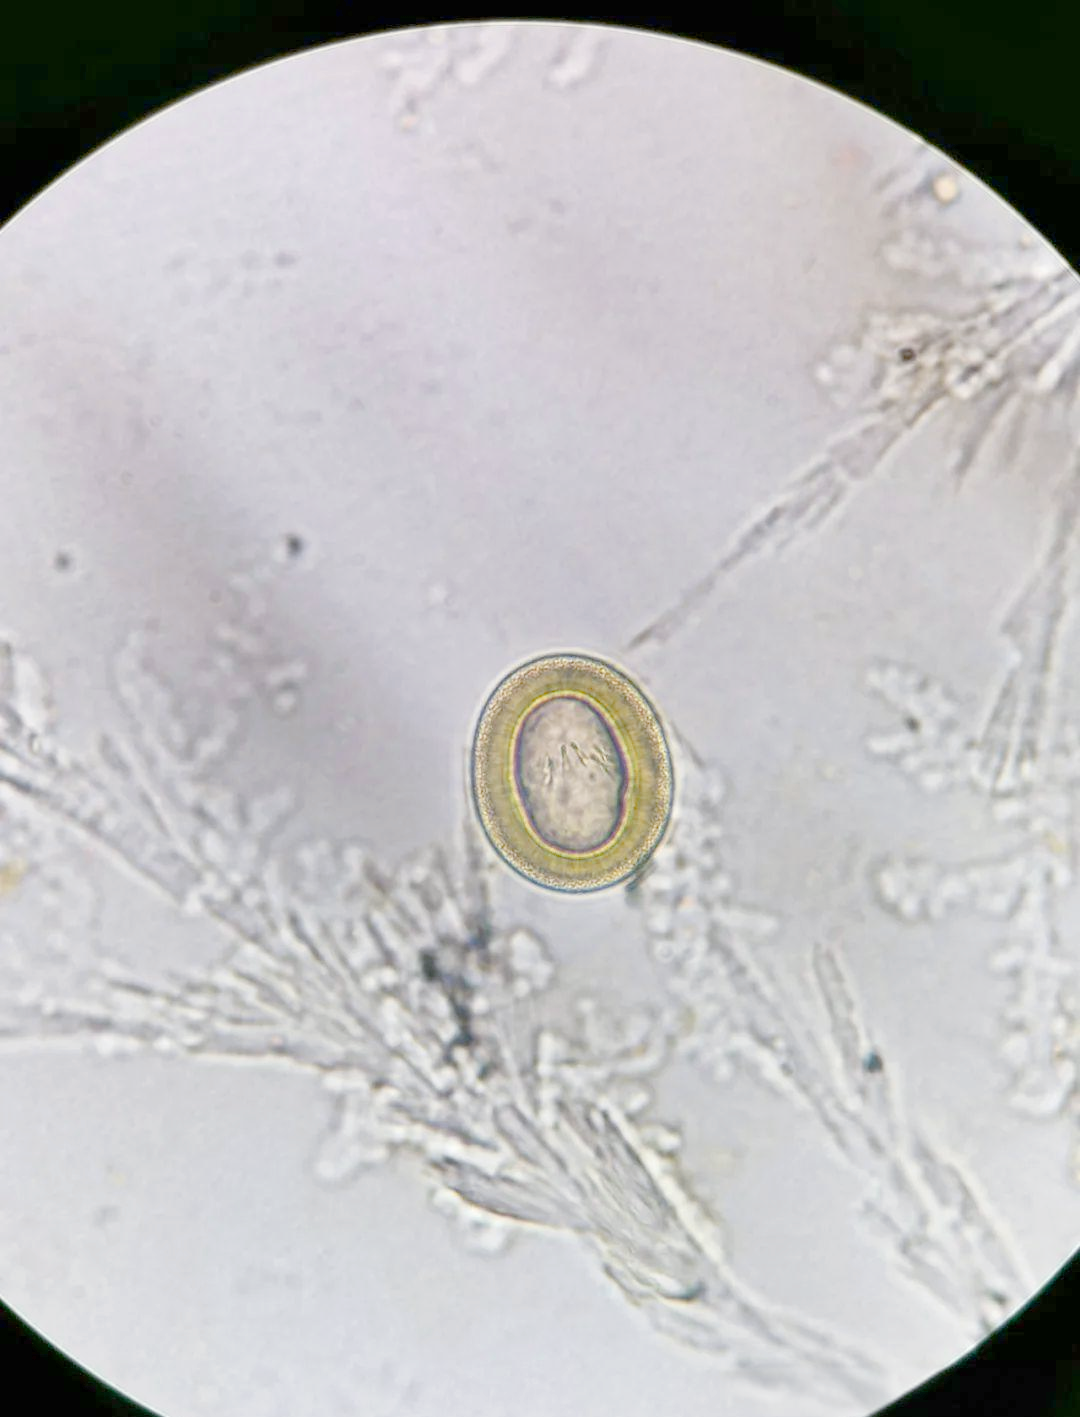

猪带绦虫卵和牛带绦虫卵在形态上非常相似,所以统称为带绦虫卵

有放射状条纹,内含一个六钩蚴,确定为带绦虫卵

猪带绦虫卵的光镜观察